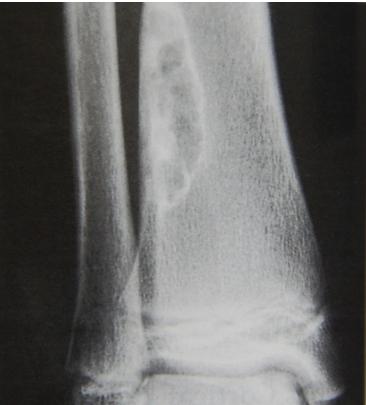

Aneurysmal Bone Cyst

site: Distal tibial

size: Involving most of distal part

matrix: Cortical expansion, radiolucent matrix, well defined, narrow zone of transition

soft tissue involvement: no peristeal reaction